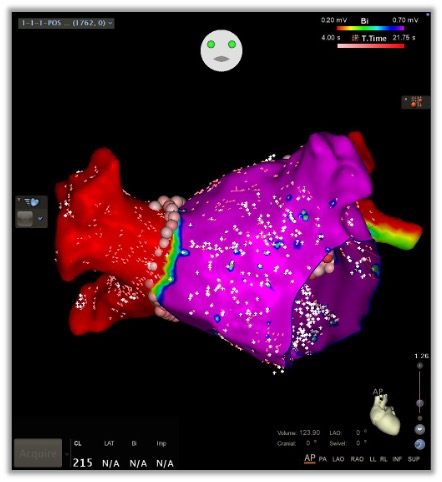

A procedure that uses energy to destroy abnormal heart tissue causing irregular rhythms.